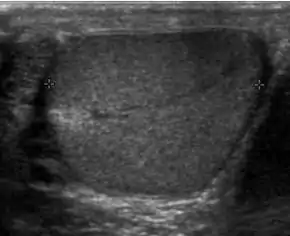

The incidence of infertility is decreased if surgical orchiopexy is carried out before the 1–3 years but the risk of malignancy does not change. Because of the superficial location of the inguinal canal in children, sonography of undescended testes should be performed with a high frequency transducer. At ultrasound, the undescended testis usually appears small, less echogenic than the contralateral normal testis and usually located in the inguinal region [Fig. 29]. With color Doppler, the vascularity of the undescended testis is poor.

Fig. 29. Undescended testis. (a) Normal testis in the scrotum. (b) Atrophic and decreased echogenicity of the contralateral testis of the same patient seen in the inguinal region.